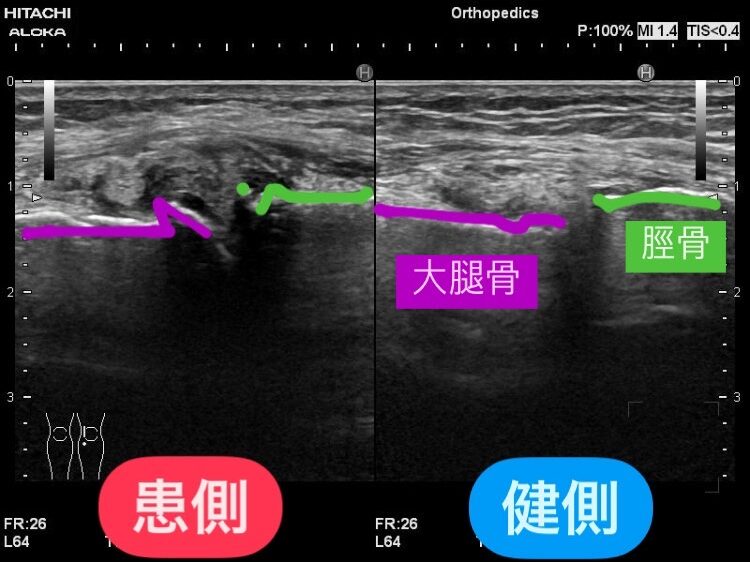

このエコー画像では、患側の関節軟骨が健側と比べると変形していて、関節周辺がローエコーで黒っぽく映り腫れていることが確認できます。